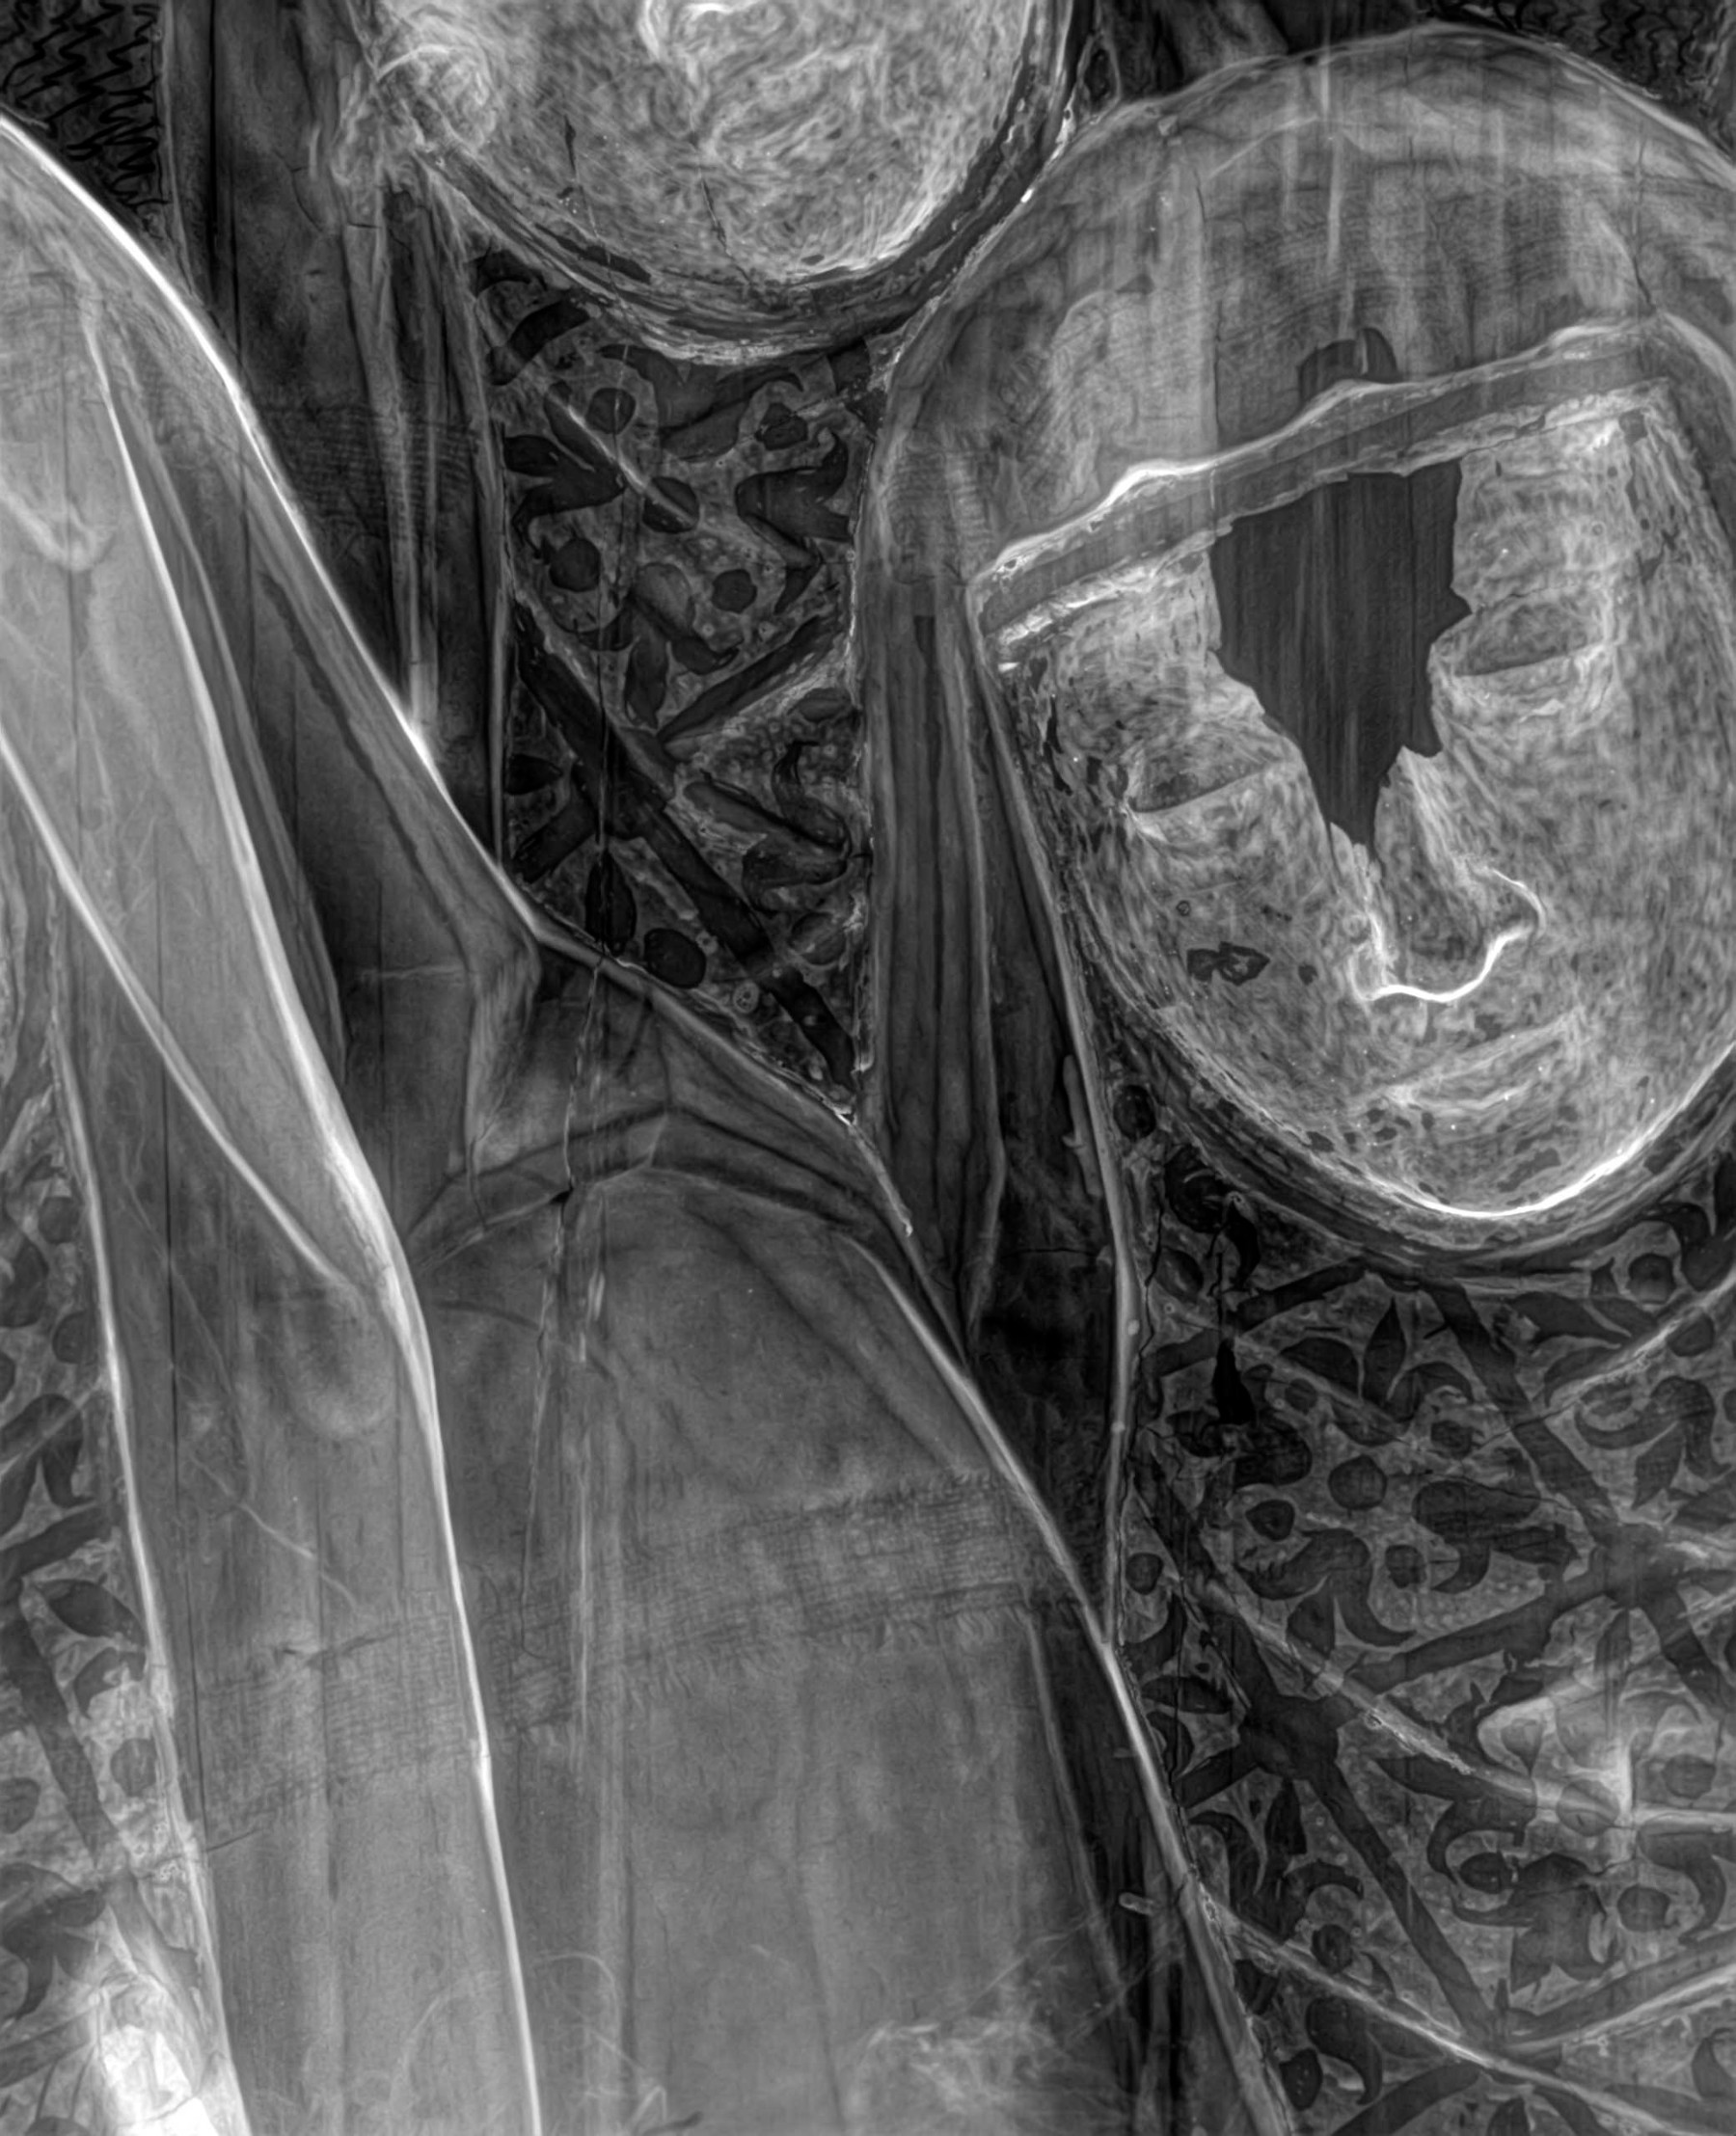

Radiología Digital como Herramienta Complementaria en el Dictamen de Bienes Muebles

Desde el descubrimiento de los rayos “X” y las placas radiográficas por Wilhelm Conrad Roentgen y su posterior difusión a través de la Asociación Físico médica de Wurzburg el 28 de diciembre de 1895, que fue la primera asociación que habló de los nuevos rayos que podían penetrar el cuerpo y fotografiar los huesos, ha habido muchos cambios tanto en la forma de obtener, procesar e incluso en la forma de visualizar, manejar y almacenar las placas radiográficas.